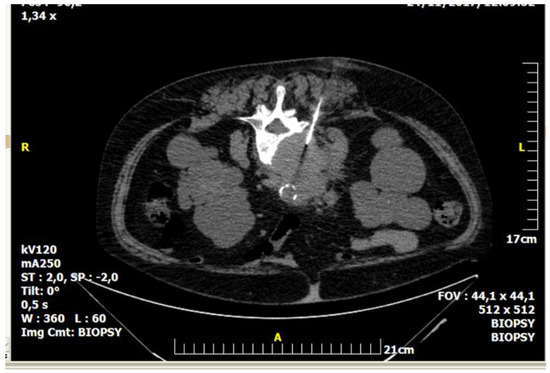

Figure 1.

A 59-year-old female patient with a medical record of urothelial carcinoma. Computed tomography axial scan: there is a soft tissue mass infiltrating the L4 vertebral body. The result of percutaneous, imaging-guided biopsy was metastasis from urothelial carcinoma.